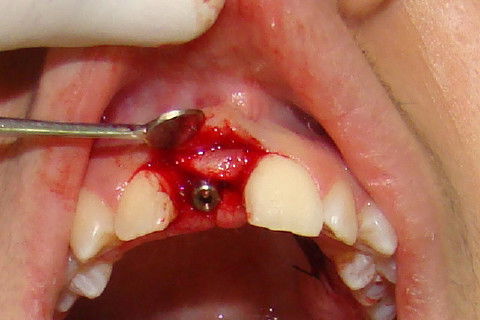

Exposição do implante, colocação de cicatrizador, antes da colocação do enxerto

Paciente com implante feito em curso de atualização, chega ao consultório para reabertura e coroa metalo-ceramica unitária, com grande depressão gengival na vestibular do elemento 11. Feita a reabertura com concomitante enxerto de tecido conjuntivo para otimizar os tecidos moles, aguardamos 3 semanas para inicio das moldagens para a coroa temporária. Após colocação e ajustes da coroa temporária parafusada, aguardamos 3 meses para completa maturação dos tecidos e então fizemos nova moldagem, com personalização do transferente para moldeira aberta individual e fizemos coros metalo-cerâmica parafusada.